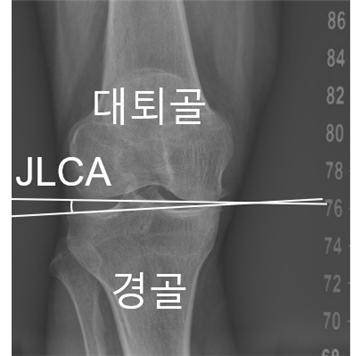

[사진] 무릎 관절선 수렴각(JLCA)

무릎 관절의 정렬 상태가 변화하는 양상과 그 변형 속도에 영향을 미치는 핵심 요인이 확인됐다. 서울대병원 연구팀은 무릎 관절을 이루는 뼈가 벌어진 정도인 ‘관절선 수렴각(JLCA)’이 이러한 변형을 가속화하는 결정적 지표라고 밝혔다.

연구팀은 무릎 관절을 이루는 대퇴골과 경골 사이의 관절선이 벌어진 정도인 ‘관절선 수렴각(JLCA)’이 이러한 가속 진행을 예측하는 공통 지표임을 밝혀냈다. 초기에 측정된 JLCA가 1° 커질 때마다 O자형 환자에서 12.9%, X자형 환자에서 19.4%씩 가속 진행 위험이 증가했다. 특히 O자형 환자의 경우 관절염 중증도가 높을수록 가속 진행 위험이 증가했으며, 중등도 이상(Grade III, IV) 단계에서는 정상군(Grade 0) 대비 약 4~5배 높은 것으로 나타났다.